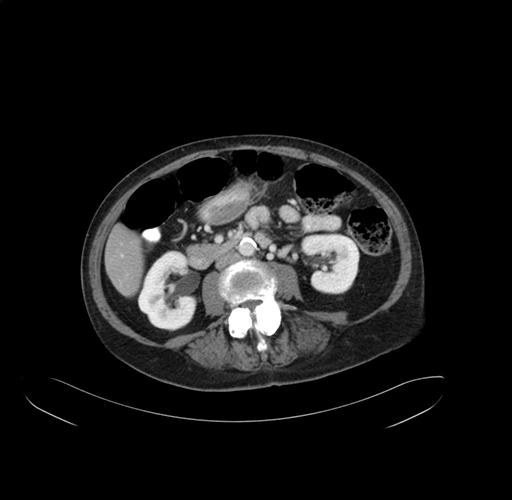

Axial Venous